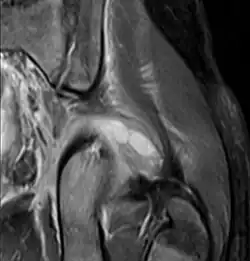

Transverse T2 magnetic resonance imaging section through the hip region showing abscess collection in a patient with pyomyositis.

Diagnostic methodDiagnostic method used for PM includes ultrasound, CT scan and MRI. Ultrasound can be helpful in showing muscular heterogeneity or a purulent collection but it is not useful during the first stage of the disease. CT scan can confirm the diagnosis before abscesses occur with enlargement of the involved muscles and hypodensity when abscess is present, terogenous attenuation and fluid collection with rim enhancement can be found. MRI is useful to assess PM and determine its localization and extension